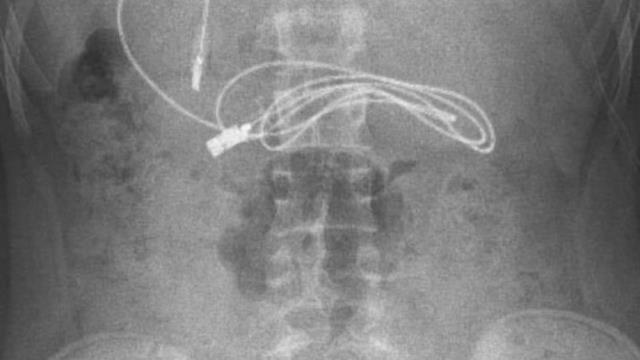

Diyarbakır'da kusma ve bulantı şikayetiyle hastaneye götürülen, çekilen röntgeninde 1 metrelik şarj kablosu ve toka yuttuğu tespit edilen 15 yaşındaki erkek çocuğu, Elazığ'da gerçekleştirilen operasyonla yuttuğu cisimlerden kurtuldu.

Diyarbakır'da kusma ve bulantı şikayetiyle ailesi tarafından hastaneye götürülen erkek çocuğunun çekilen röntgeninde, midesinde şarj kablosu ve toka olduğu tespit edildi. Bunun üzerine çocuk, ambulans ile Fırat Üniversitesi Hastanesi'ne sevk edildi. Üniversitenin Çocuk Gastroenteroloji Hepatoloji ve Beslenme Bilim Dalı Başkanı Prof. Dr. Yaşar Doğan ve ekibi tarafından yapılan endoskopik işlemle çocuğun midesindeki kablo ve toka başarıyla çıkarıldı. Tedavisinin ardından sağlığına kavuşan çocuk taburcu edildi.

Ameliyatı gerçekleştiren Prof. Dr. Yaşar Doğan, kablonun bir ucunun ince bağırsağa geçmesi nedeniyle zorlandıklarını ifade ederek, "Hastanın kusma ve karın ağrısı şikayetleri olması üzerine sağlık kuruluşuna başvurulmuş. Orada yapılan incelemelerde hastanın midesinde kablo tespit edilmesi üzerine bize danışıldı. 112 aracılığıyla hastaya gerekli işlemi yapıp yapmayacaklarını bize sordular. Biz de hastayı bize gönderebileceklerini kendilerine ilettik. Hasta bize geldikten sonra ön hazırlık yapıldı ve gerekli olan açlık süresinin ardından hastaya endoskopik işlem yapıldı. Endoskopik işlemle midedeki kablo çıkarıldı. Kabloyu çıkarırken açıkçası zorlandık, çünkü kablonun bir ucu ince bağırsağa geçmişti. İşlem başarılı bir şekilde sonlandırıldıktan sonra hasta sağlıklı bir şekilde evine gönderildi" dedi.